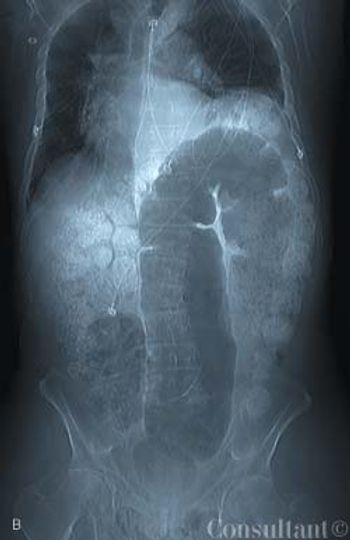

A 68-year-old man with a prosthetic mitral valve presents to the emergency department with acute abdominal pain, nausea, vomiting, and constipation. Surgical evaluation is performed; the results suggest a complete bowel obstruction. Urgent celiotomy is recommended.